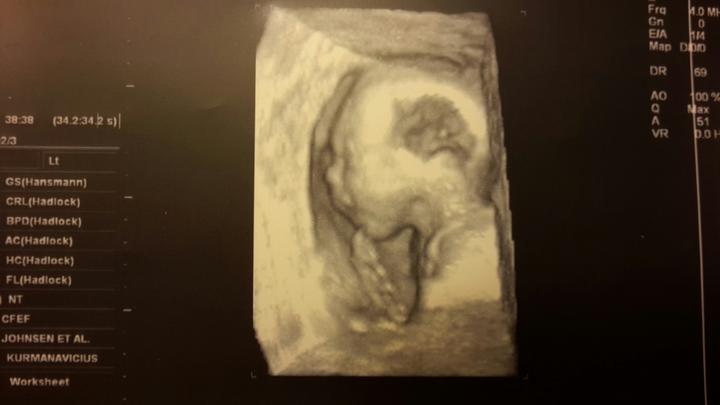

Tak dneska 3D ultrazvuk a 100% kluk 🙂

(3 fotky)